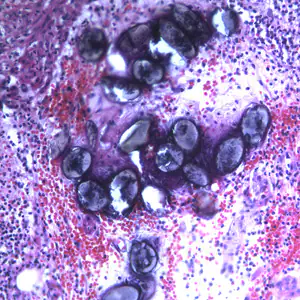

A. lumbricoides in tissue specimens.